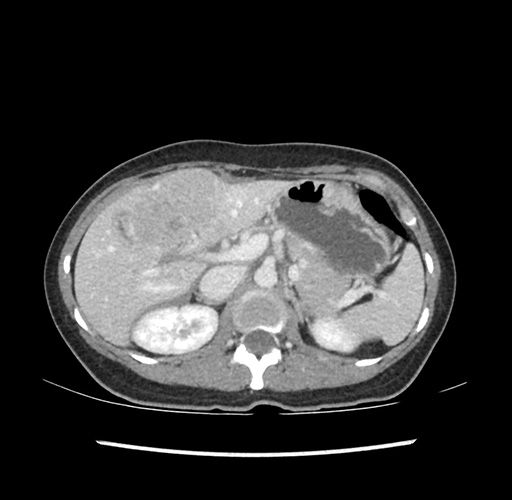

Imaging Analysis

Look through the patient's CT scan to identify any areas of concern for the necessary procedure.

Based on your CT findings, which issue(s) would give reason for "planned slowing down moment(s)" in this case?

Considering a standard left lateral sectionectomy procedure, what step(s) of the operation would you do differently in this case ?